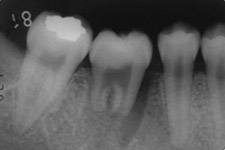

a、b: 治療前。16歳、少女。

第二大臼歯が吸収を受けており保存が不可能でした。そこで、隣接する親知らずを同部へ移植することにしました。

c : 移植直後

d : 移植後3ヶ月